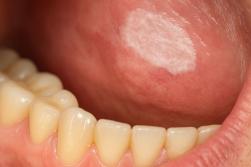

Tache blanche dans la bouche: attention à la leucoplasie

Une leucoplasie se présente sous forme de plaque blanche qui ne disparaît pas au grattage. Elle n’est pas forcément douloureuse, et c’est justement ce qui la rend trompeuse: on peut vivre avec sans y prêter attention.